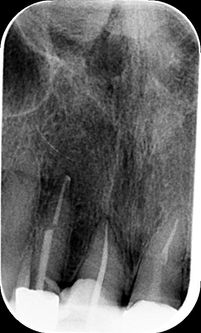

Root Canal Obliteration

Root canal obliteration can occur after a tooth has received some trauma in the past. The tooth canal gets smaller over time, to the point it is microscoptic. Normally the tooth stay symptom free however if the tooth finally dies and needs root canal treatment it can be challenging to get into the canal system.